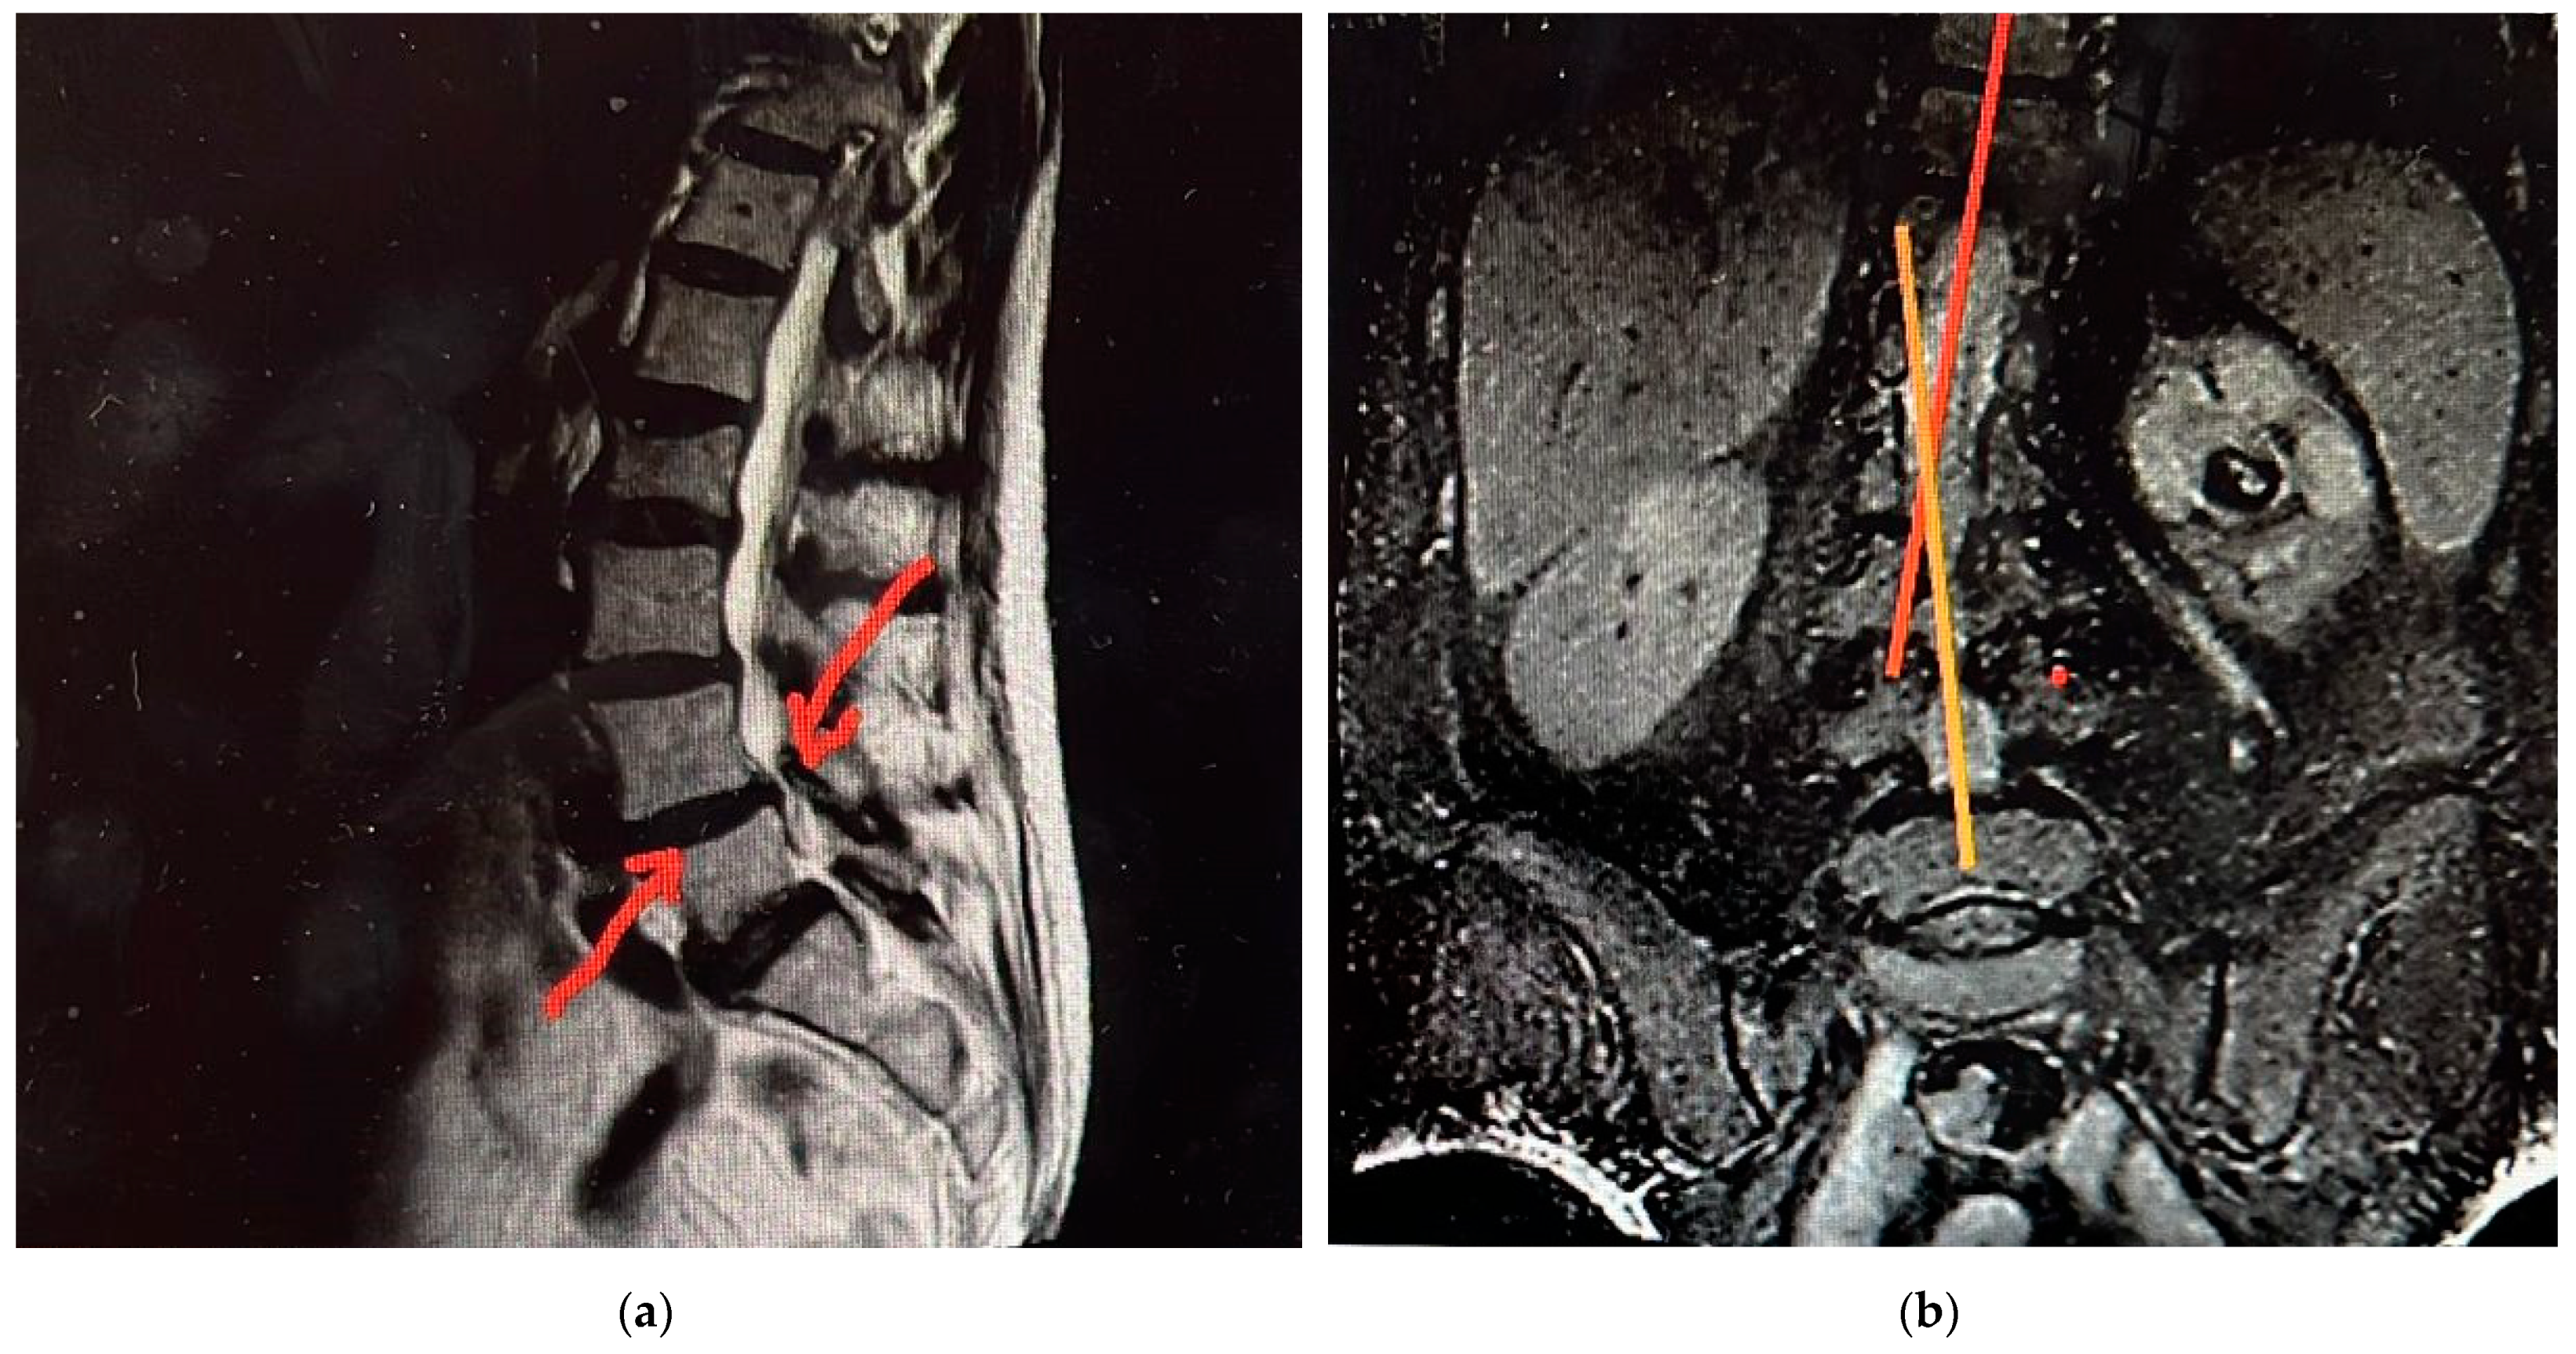

- imaging and spectral techniques in support of primary X-ray radiographs, to get a more precise picture of the case and diagnostic.